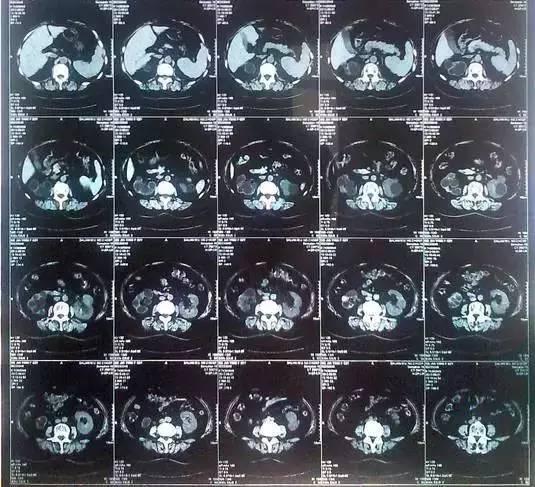

55歲的老何是金華東陽市橫店鎮(zhèn)人,一名普通工人。因為頻繁腰疼去醫(yī)院檢查,結果CT顯示,他的左腎里竟然密密麻麻布滿了石頭,幾乎把整個腎都塞滿了,手術從左腎取出了420顆結石!

醫(yī)生看了CT的結果顯示,非常嚴肅的告訴他,他的左腎已經被結石占滿,必須馬上手術治療。這次手術讓主刀醫(yī)生觸目驚心,他們居然從老何的左腎取出了420顆結石。這是他們手術生涯上從來沒有遇到過的病例。